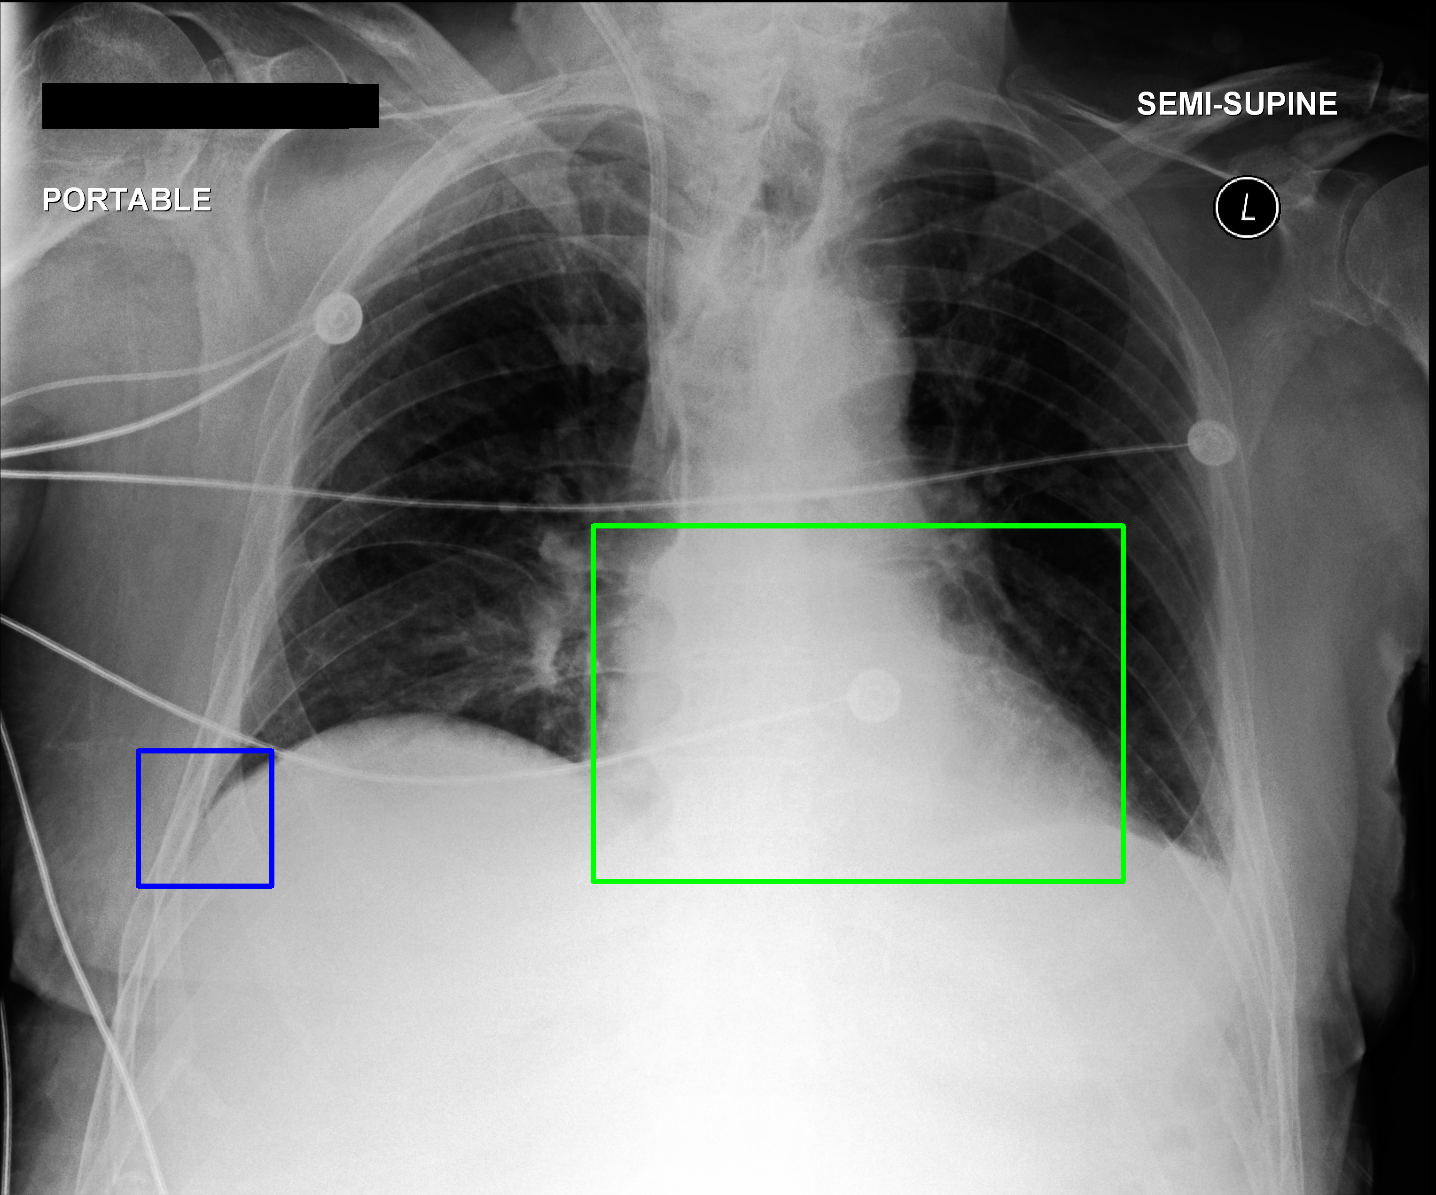

Image 2 RCA LCA

[Uncaptioned image] [Uncaptioned image] [Uncaptioned image]

Ground Truth L2 L2

CheXGCN No findings No findings

AnaXNet L2 L2

Figure 2: Examples of the results obtained by our best two models. The overall chest X-ray image is shown alongside two anatomical regions. The predictions from best performing models are compared against the ground-truth labels.

The CheXGCN model outperforms the other two baselines but is also limited because it focuses on one section and uses label dependencies to learn the relationship between the labels, while ignoring the relationships between the anatomical regions of the chest X-ray image. In Table 2, we visualize the output from both the CheXGCN model and our AnaXNet model. The CheXGCN model had difficulty predicting small anatomical regions like the costophrenic angles, while our model had additional information from the remaining anatomical regions, which helped in its prediction. Also the CheXGCN model struggled with enlarged cardiac silhouette label because information from the surrounding labels is needed in order to accurately tell if the heart is enlarged.